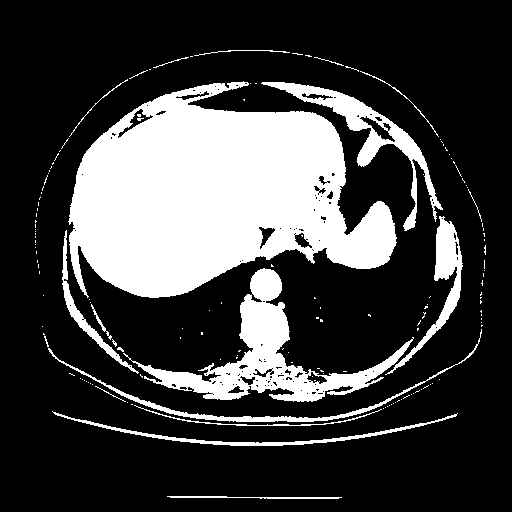

Generated VENOUS CT scan (A→B translation)

Full window (WL 1023.5, WW 4095 β†’ Low βˆ’1024, High +3071)

Actual HU range: [-1024.0, 3071.0]